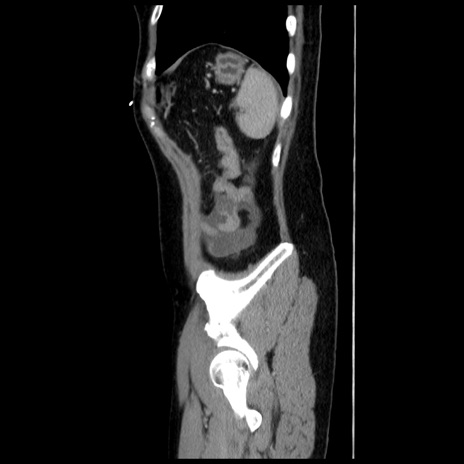

横断像

冠状断像